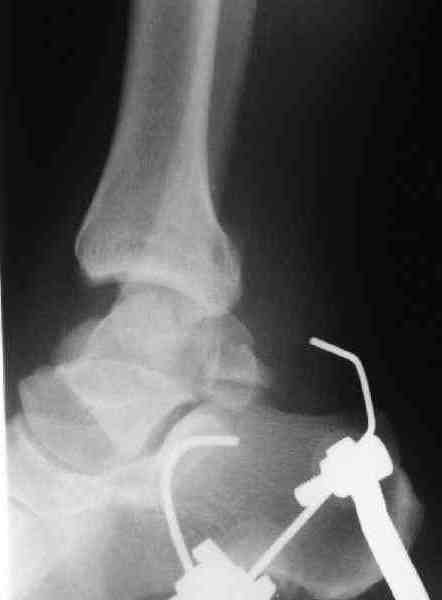

Решили не связываться с остеосинтезом, а сделать сразу берцово-пяточный блок. Снимки в приложении.

По завершении удлинения, наверно, заштифтуем.

Комментарии/критика приветствуются.